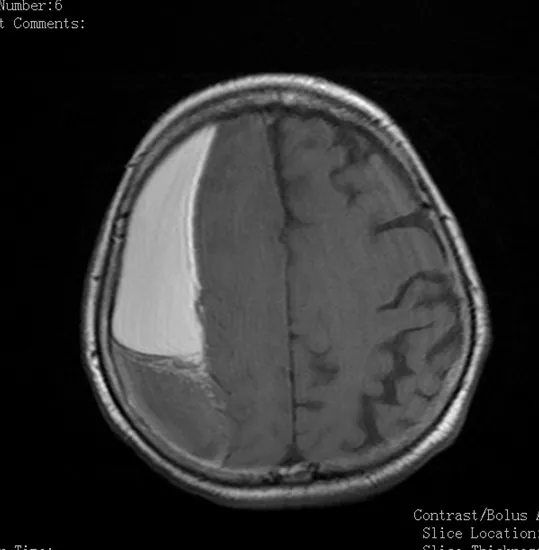

Медицинские аспекты и диагностика субдуральной гигромы мозга